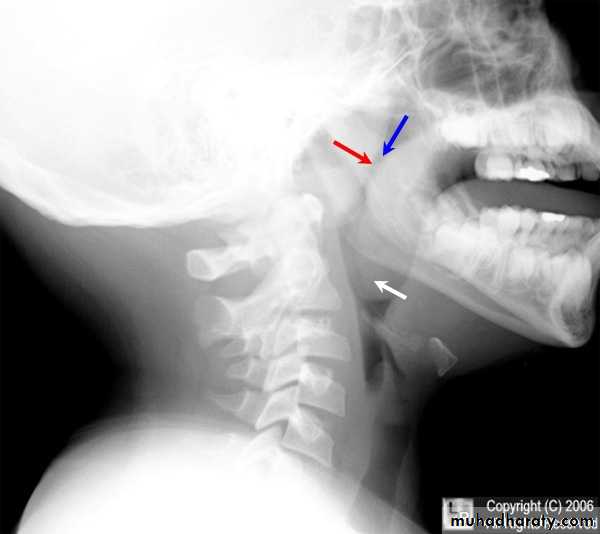

Radiography:Plain films like lateral X-Ray of the skull, is needed in nasopharyngeal mass like adenoids, and can demonstrate bone erosion in cases of nasopharyngeal cancer.

3. Posterior rhinoscopy and fibroptic endoscopy: lobulated mass, which occasionally extends laterally.Investigations

X-ray of the postnasal spaceComplications